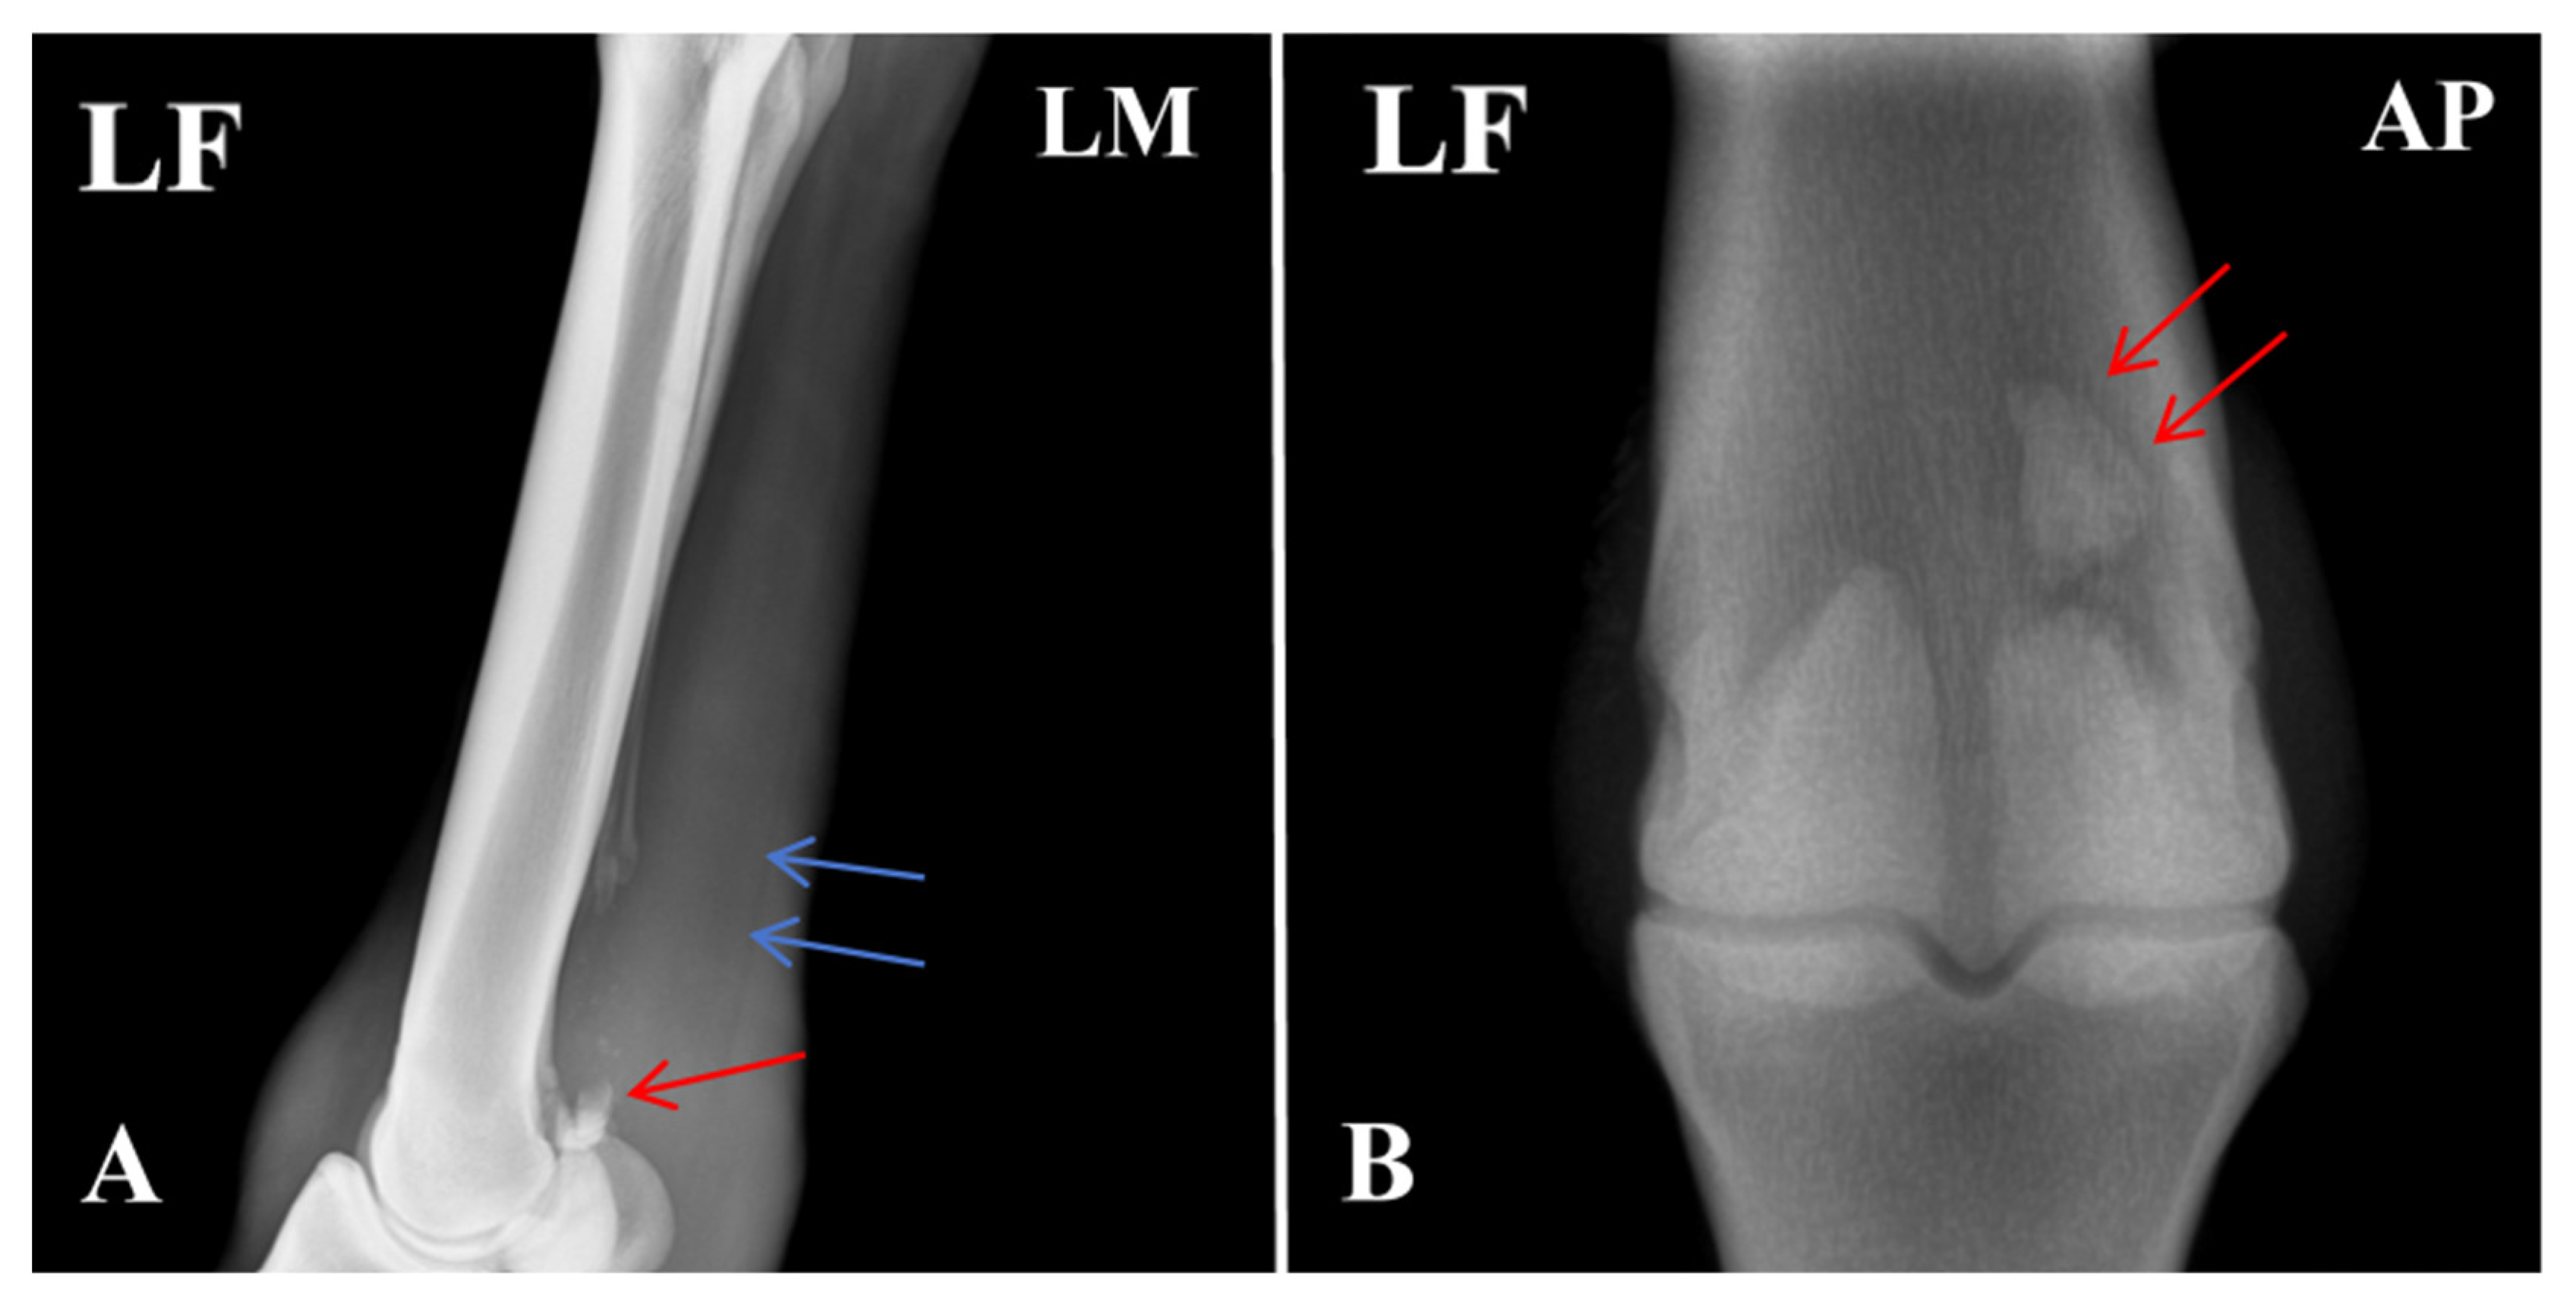

Radiographic evaluation was performed to assess the type of lesion and to determine whether flexor tendinitis was present. Images were taken of the left forelimb (LF) in lateromedial (LM) and dorsopalmar/anteroposterior (AP) projections. The radiographs showed a clear fracture line at the proximal apex of the left proximal sesamoid bone, with separation of the fracture margins and the presence of a small free bone fragment. The fragment had an irregular shape and was displaced away from the main sesamoid body. Local cortical continuity was disrupted, and the trabecular pattern appeared disorganized. An increase in soft-tissue density was also noted in the flexor tendon region, raising suspicion of concurrent flexor tendinitis (Figure 2).

Figure 2. Radiographic features of the affected horse with PSBF. (A) Fracture at the apex of the proximal sesamoid bone (red arrow: bone fragments; blue arrow: increased radiodensity in the flexor tendon region). (B) Fracture fragments of the proximal sesamoid bone. The arrows indicate the specific lesions.